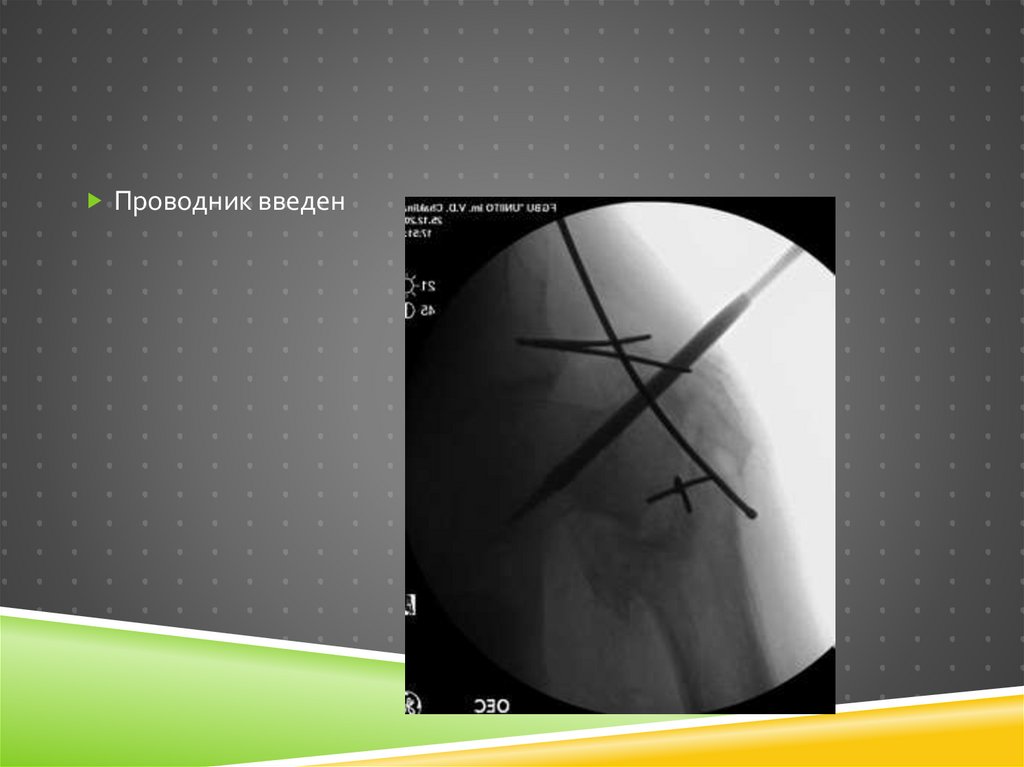

Проводник введен